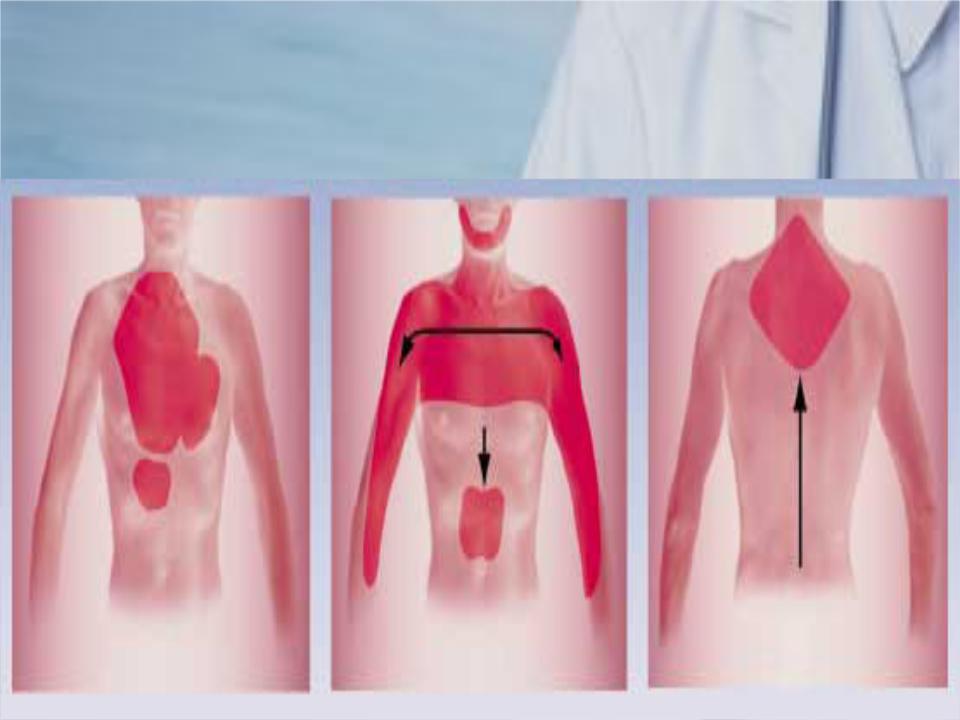

Причины и лечение боли в грудной клетке при кашле